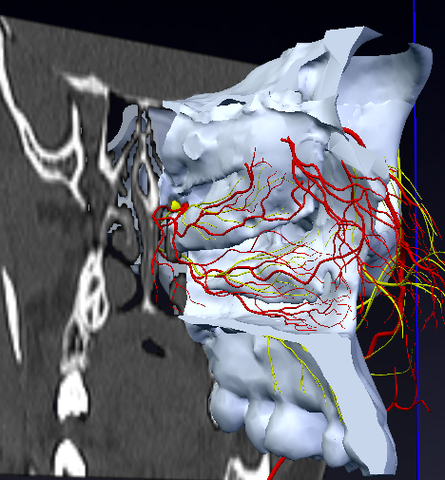

Ligadura de la arteria maxilar interna.

Muy utilizada antes del advenimiento de la cirugía endoscopica nasal. Actualmente sólo se usa en casos selectos principalmente de origen tumoral debido a la complejidad anatómica de la región.